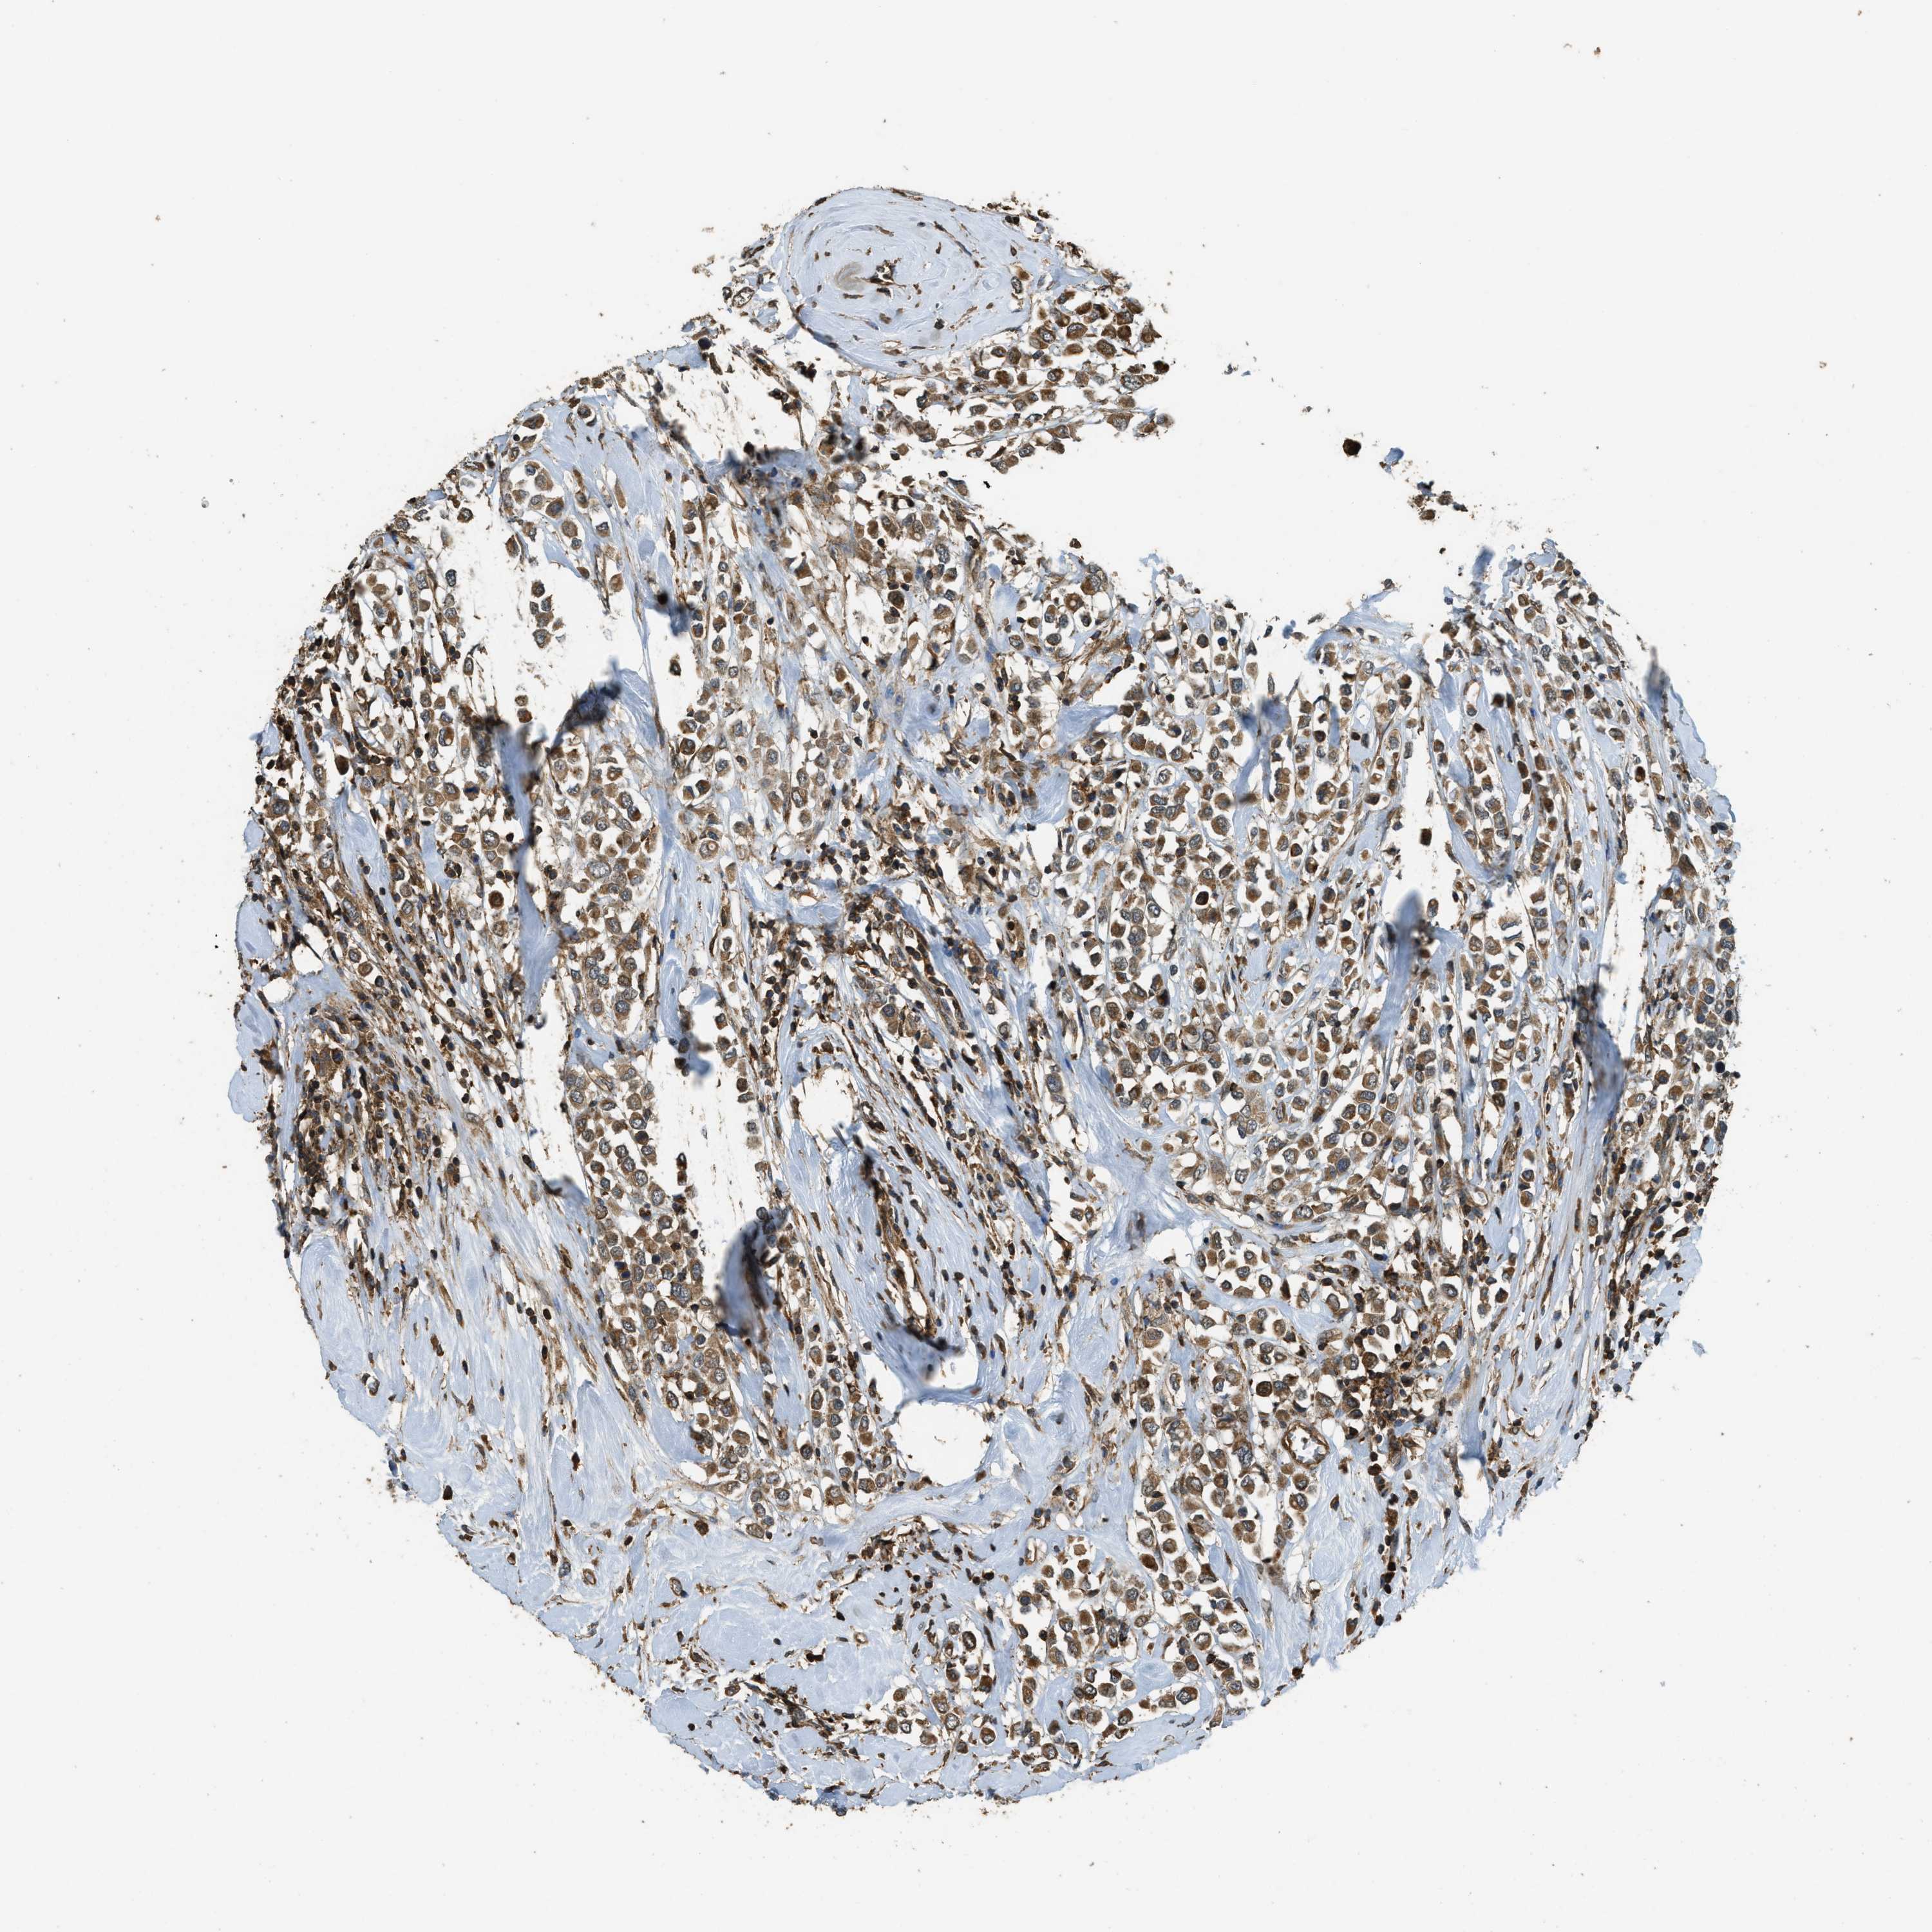

BRCA TCGA BRCA VALIDATION PROTEIN EXPRESSION

ANTIBODIES

AND

VALIDATION